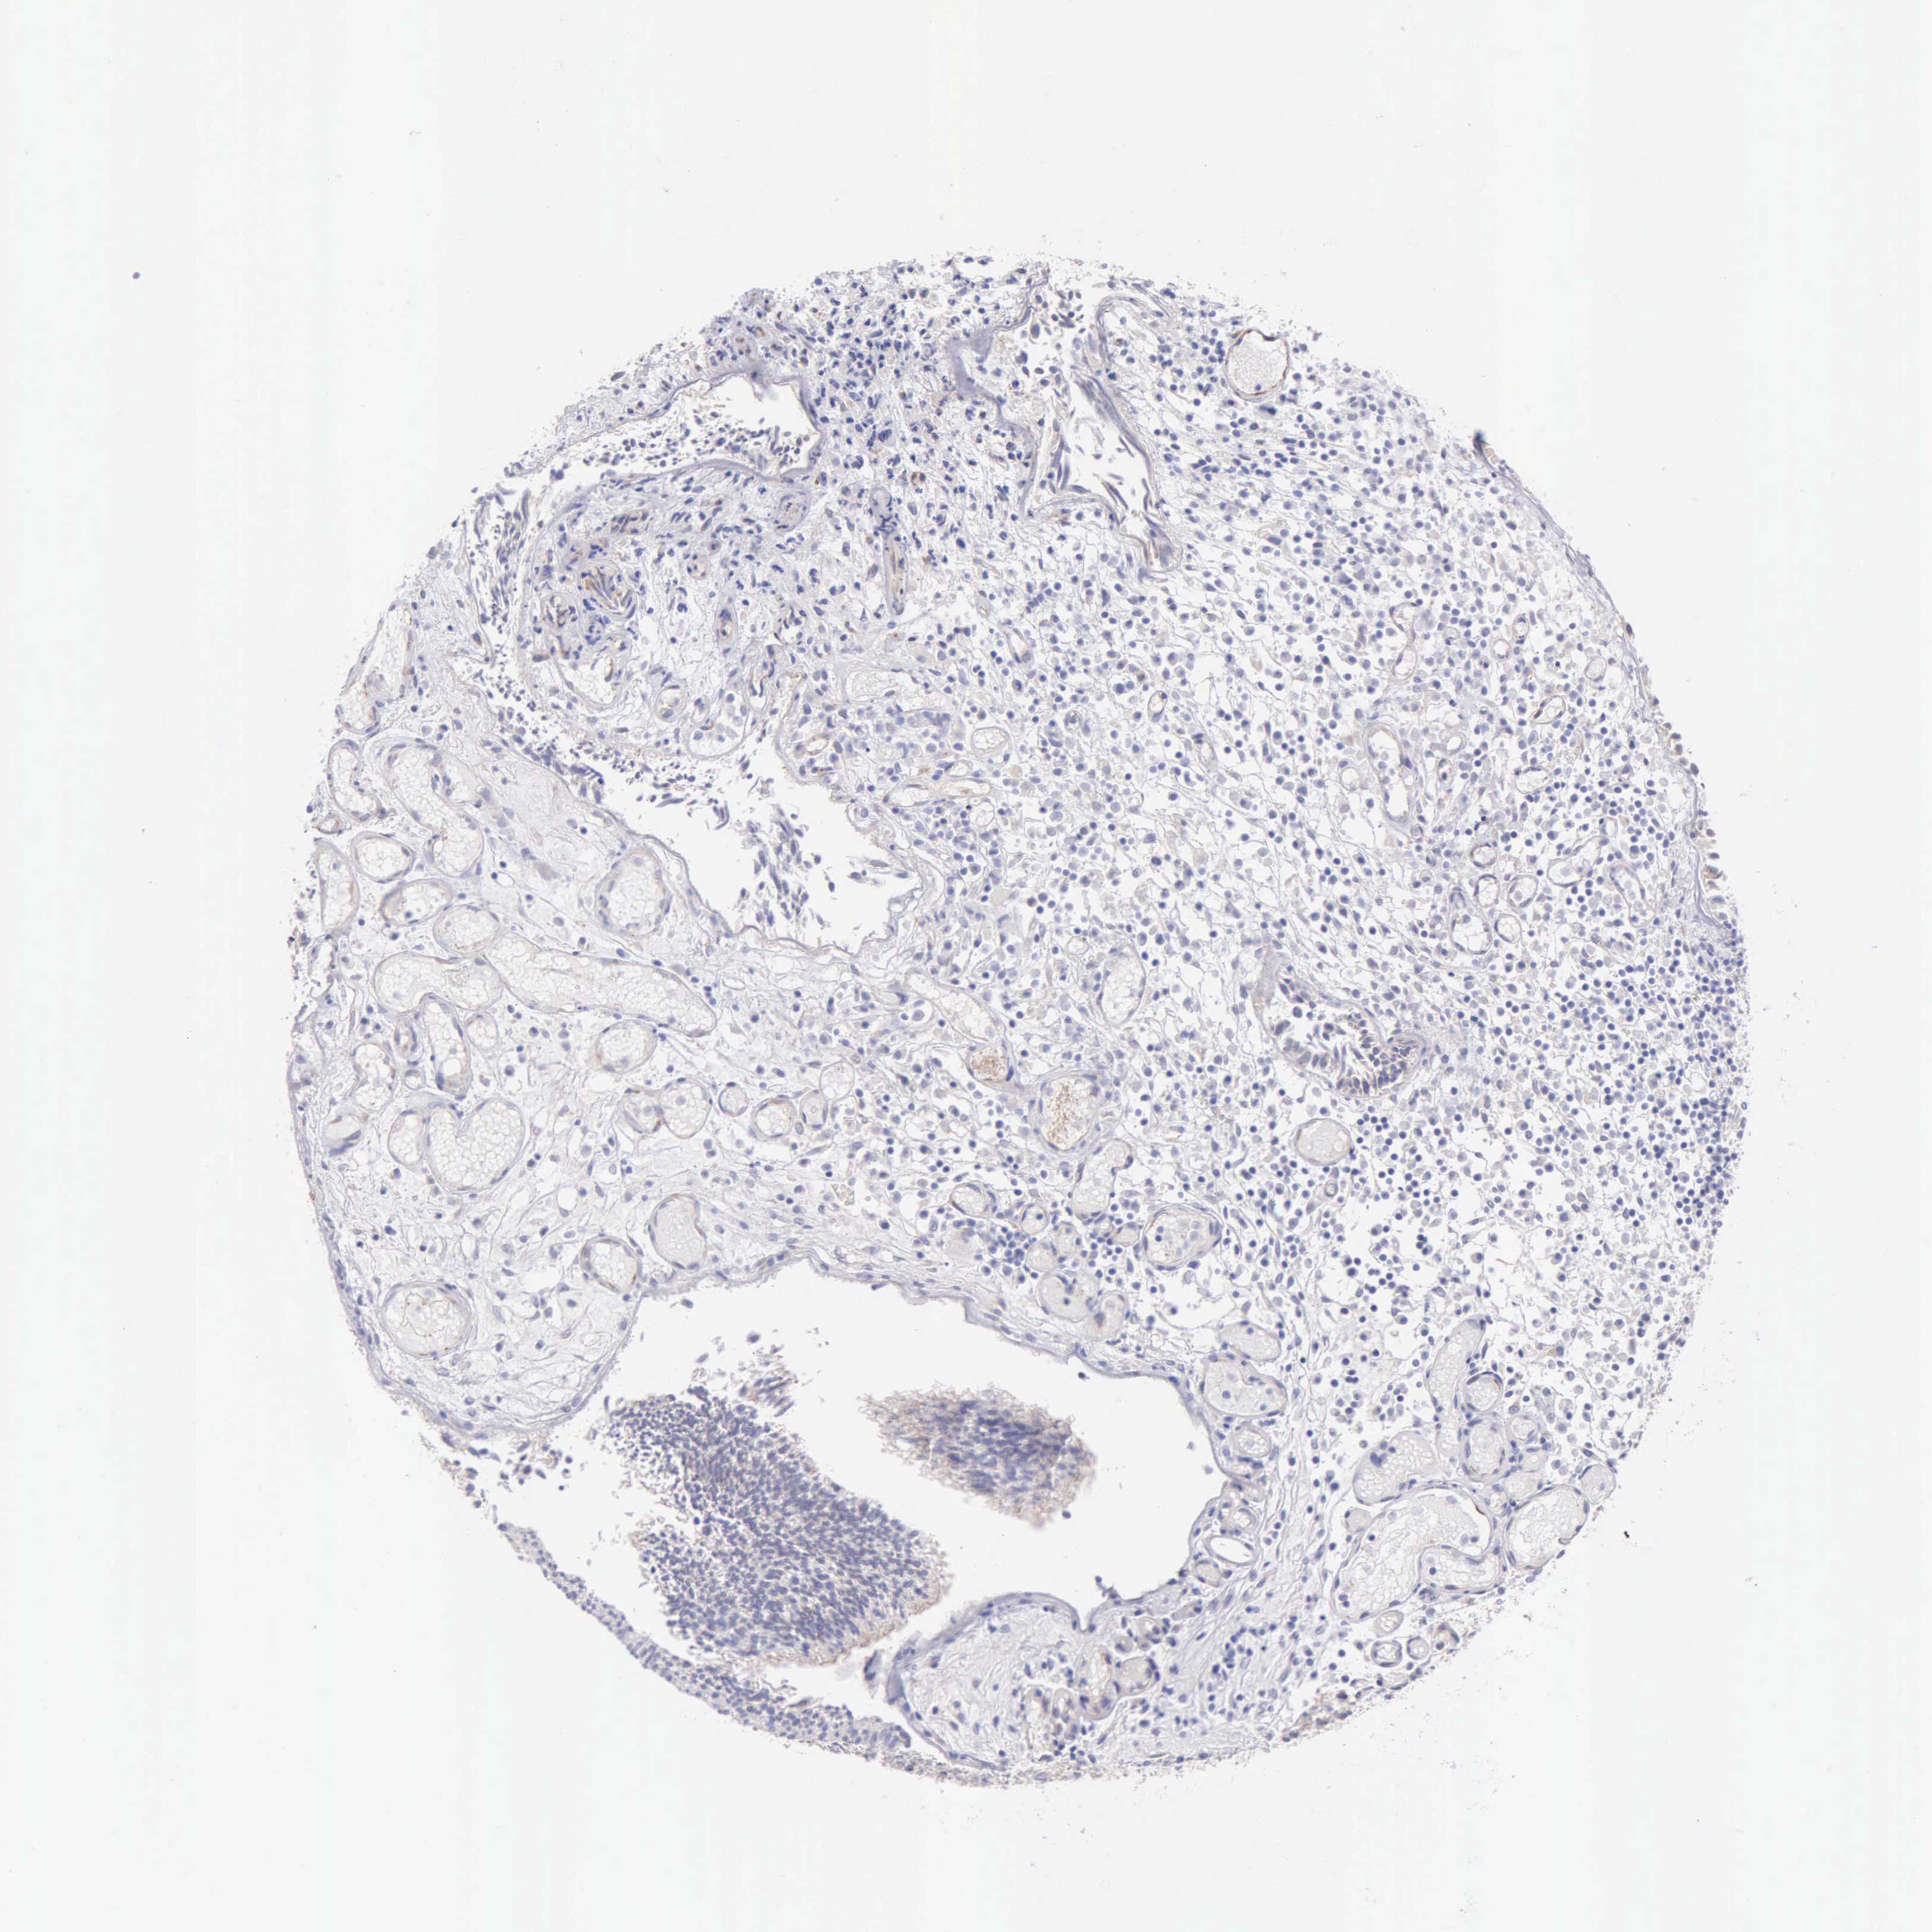

UROTHELIAL CANCER - Protein expressioni

A mouse-over function shows sample information and annotation data. Click on an image to view it in a full screen mode. Samples can be filtered based on level of antibody staining by selecting one or several of the following categories: high, medium, low and not detected. The assay and annotation is described here.

Antibody stainingi

Antibody staining in the annotated cell types in the current human tissue is reported as not detected, low, medium, or high, based on conventional immunohistochemistry profiling in selected tissues. This score is based on the combination of the staining intensity and fraction of stained cells.

Each image is clickable and will lead to virtual microscopy that enables deeper exploration of all samples and also displays staining intensity scores, fraction scores and subcellular localization as well as patient and tissue information for each sample.

Antibody HPA001462

Antibody CAB000157

Urothelial carcinoma, High grade

Urothelial carcinoma, Low grade

Adenocarcinoma, NOS